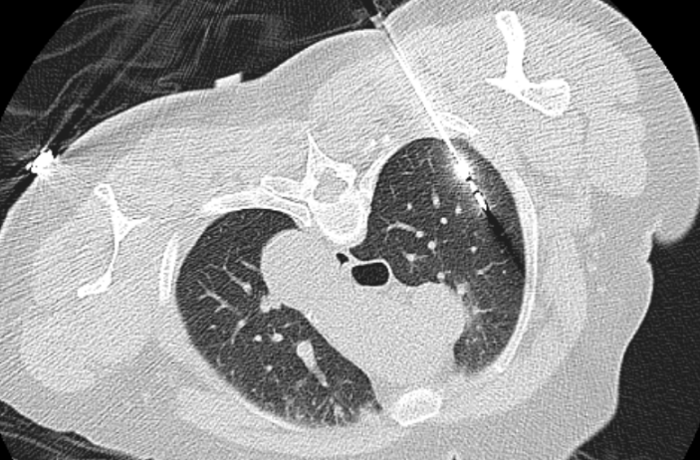

当天,心胸外科主任阳诺带领消融团队开展手术。他介绍,在术前,穿刺手术机器人系统基于患者CT影像,能自动构建详细的肺部3D立体模型,清晰呈现结节与周围血管、气管等重要组织的位置关系。

快速精准定位一直是肺结节介入诊疗的核心环节。目前CT引导下经皮肺肿瘤消融治疗、经皮肺结节穿刺定位术、经皮肺肿瘤穿刺活检术等均依赖于高超精准的穿刺技术。传统穿刺方式高度依赖操作者的手感与临床经验,精准的穿刺技术学习周期长,对于刚接触肺肿瘤穿刺技术的医生,实际操作穿刺路径可偏离靶病灶几度甚至到十几度,从而导致多次CT扫描并反复调针,耗时长,还会增加出血、气胸等并发症发生率及辐射暴露。而机器人穿刺导航系统可复刻规划好的穿刺路径,彻底改变了传统操作模式。

▲术前穿刺规划路径